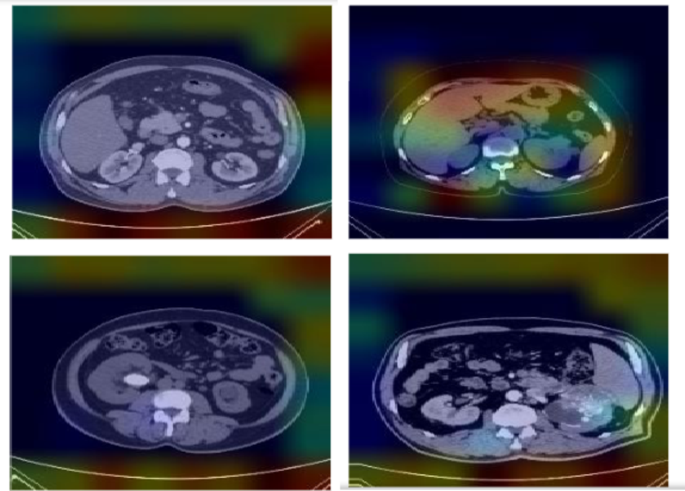

The interpretability of the proposed model is illustrated through Gradient-weighted Class Activation Mapping (Grad-CAM) and SHAP visualisation techniques. Grad-CAM18 highlights important regions in images that significantly impact the model’s predictions for every class. SHAP visualisation offer visual representation that indicate the importance of specific regions on the model’s decisions, enhancing its interpretability. Figures 10 and 11 shows the features obtained using SHAP15 and Grad-CAM showcasing the interpretability of the proposed work.